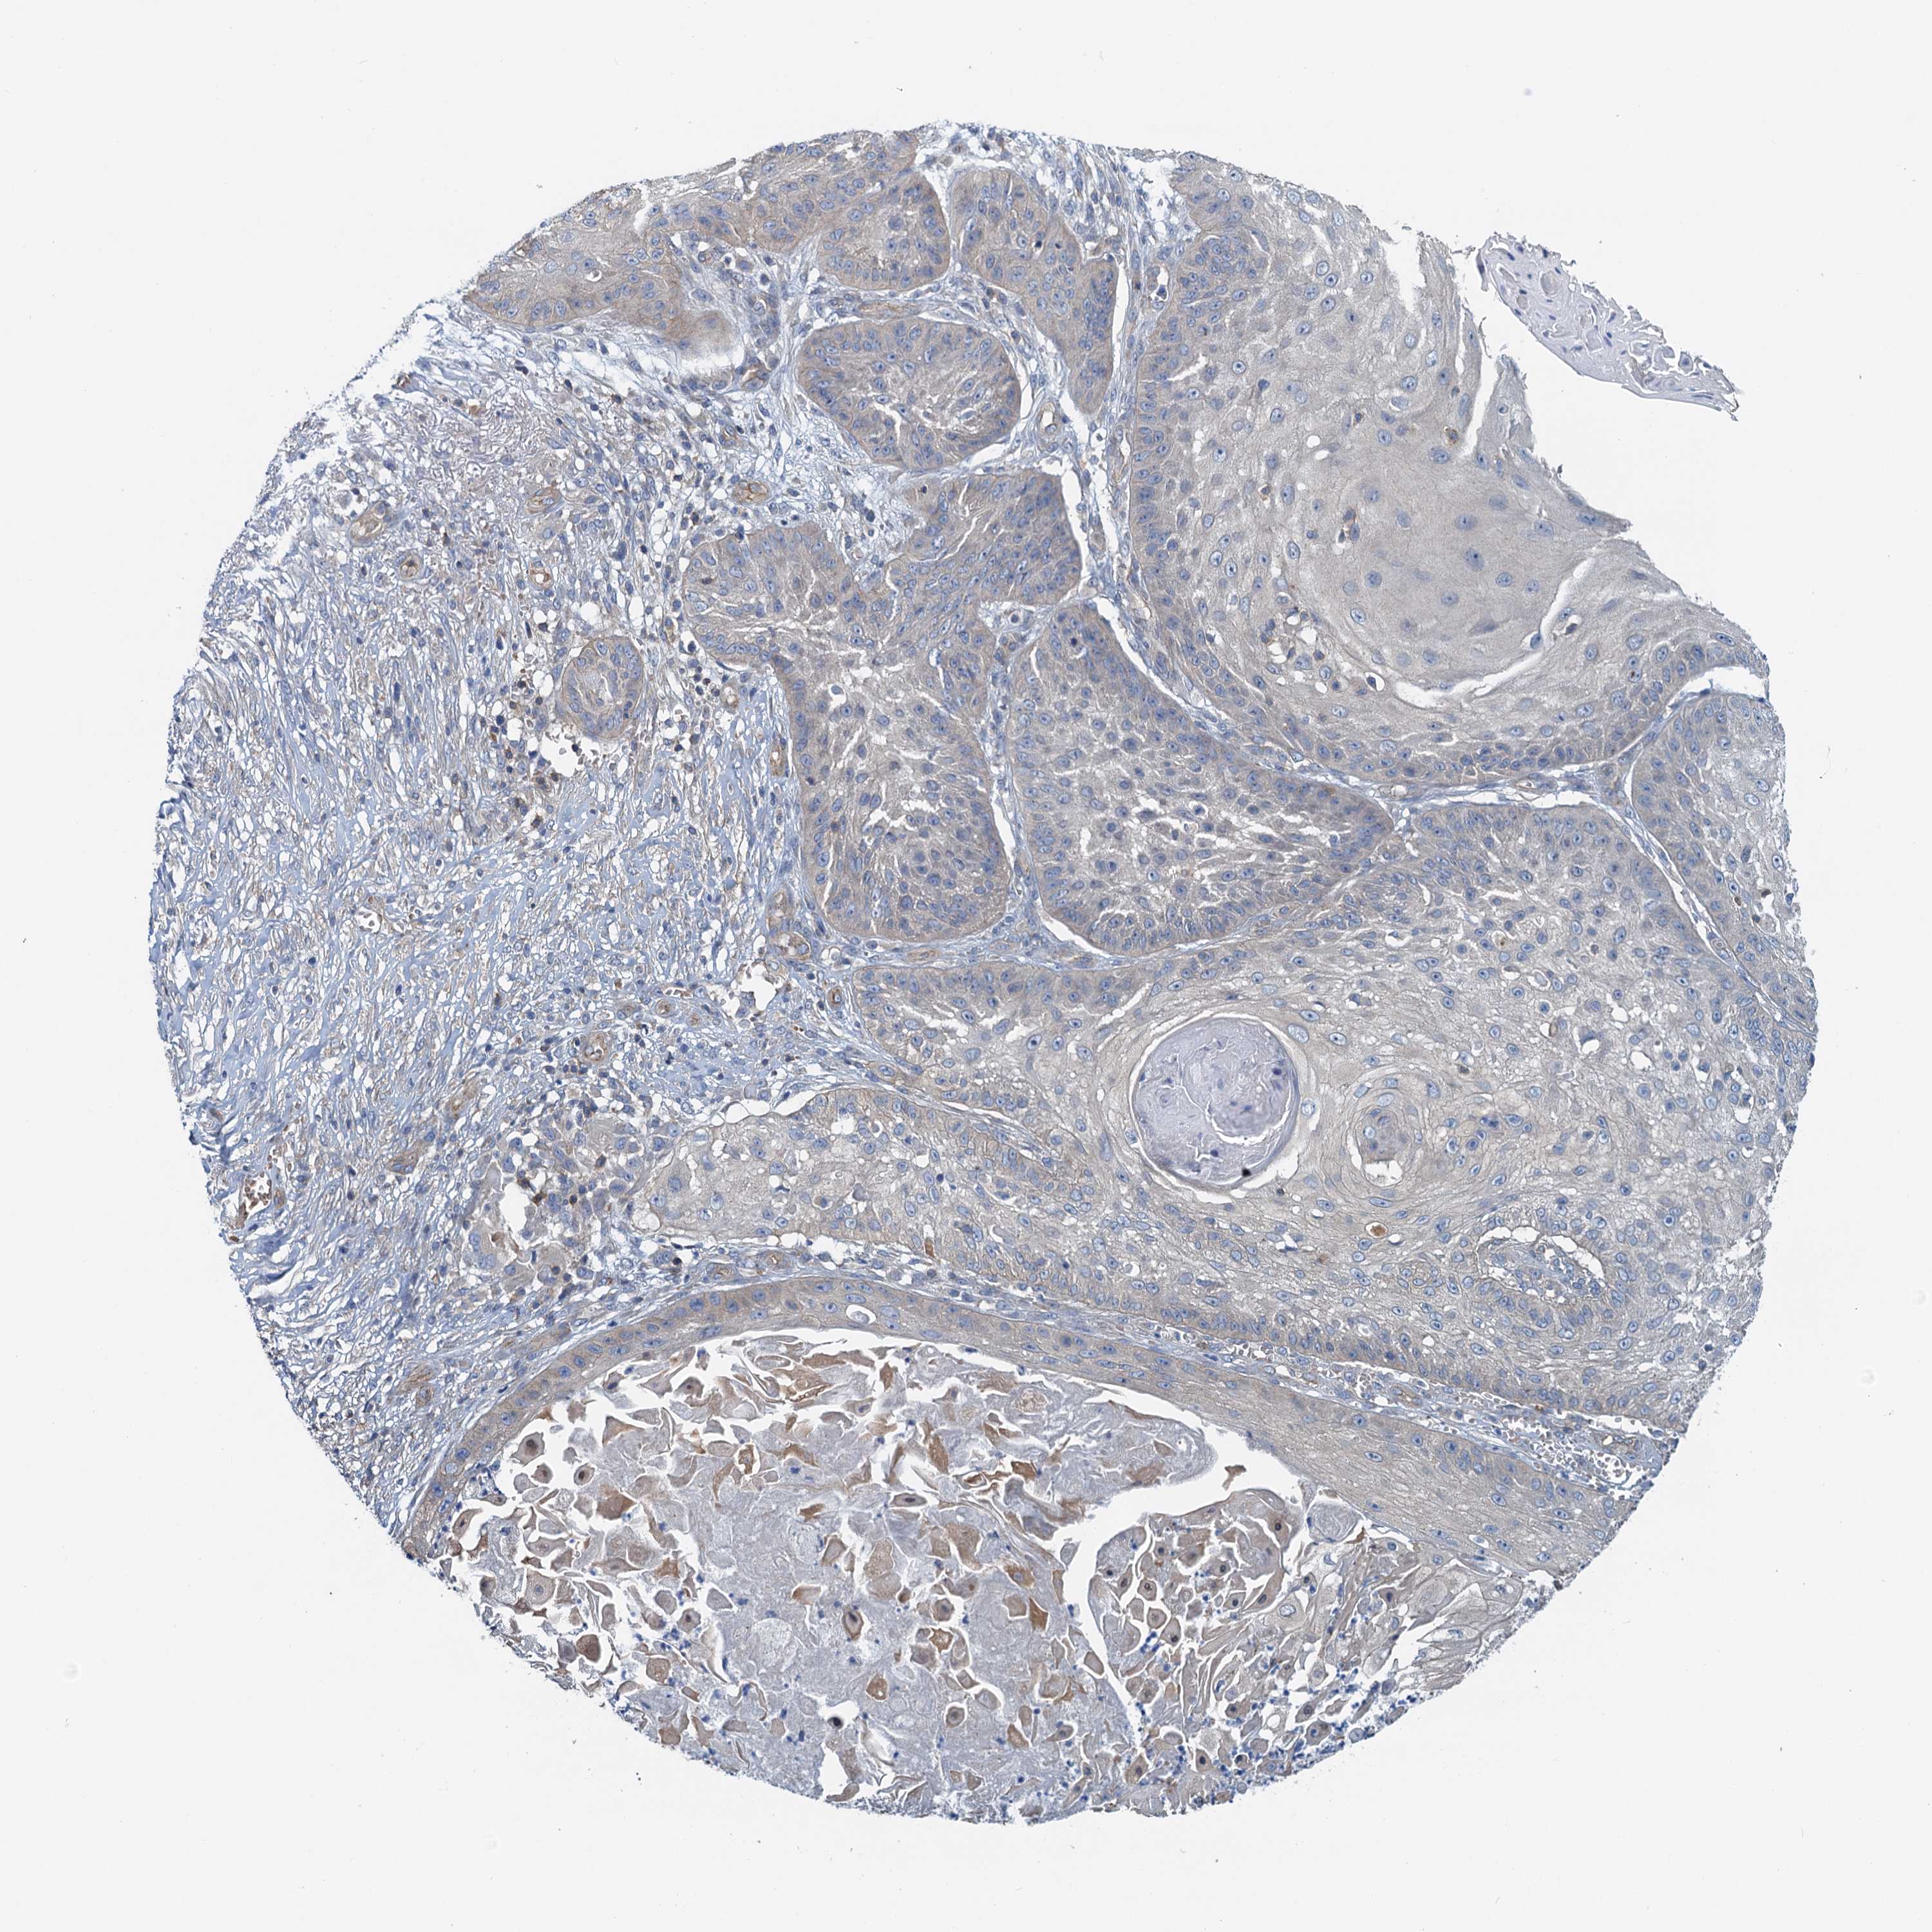

Basal cell and squamous cell cancer

SKIN CANCER - Protein expressioni

A mouse-over function shows sample information and annotation data. Click on an image to view it in a full screen mode. Samples can be filtered based on level of antibody staining by selecting one or several of the following categories: high, medium, low and not detected. The assay and annotation is described here.

Each image is clickable and will lead to virtual microscopy that enables deeper exploration of all samples and also displays staining intensity scores, fraction scores and subcellular localization as well as patient and tissue information for each sample.

Antibody HPA041000

Staining

High

Medium

Low

Not detected

Intensity

Strong

Moderate

Weak

Negative

Quantity

>75%

75%-25%

<25%

None

Location

Nuclear

Cytoplasmic/membranous

Cytoplasmic/membranous,nuclear

Squamous cell carcinoma, NOS